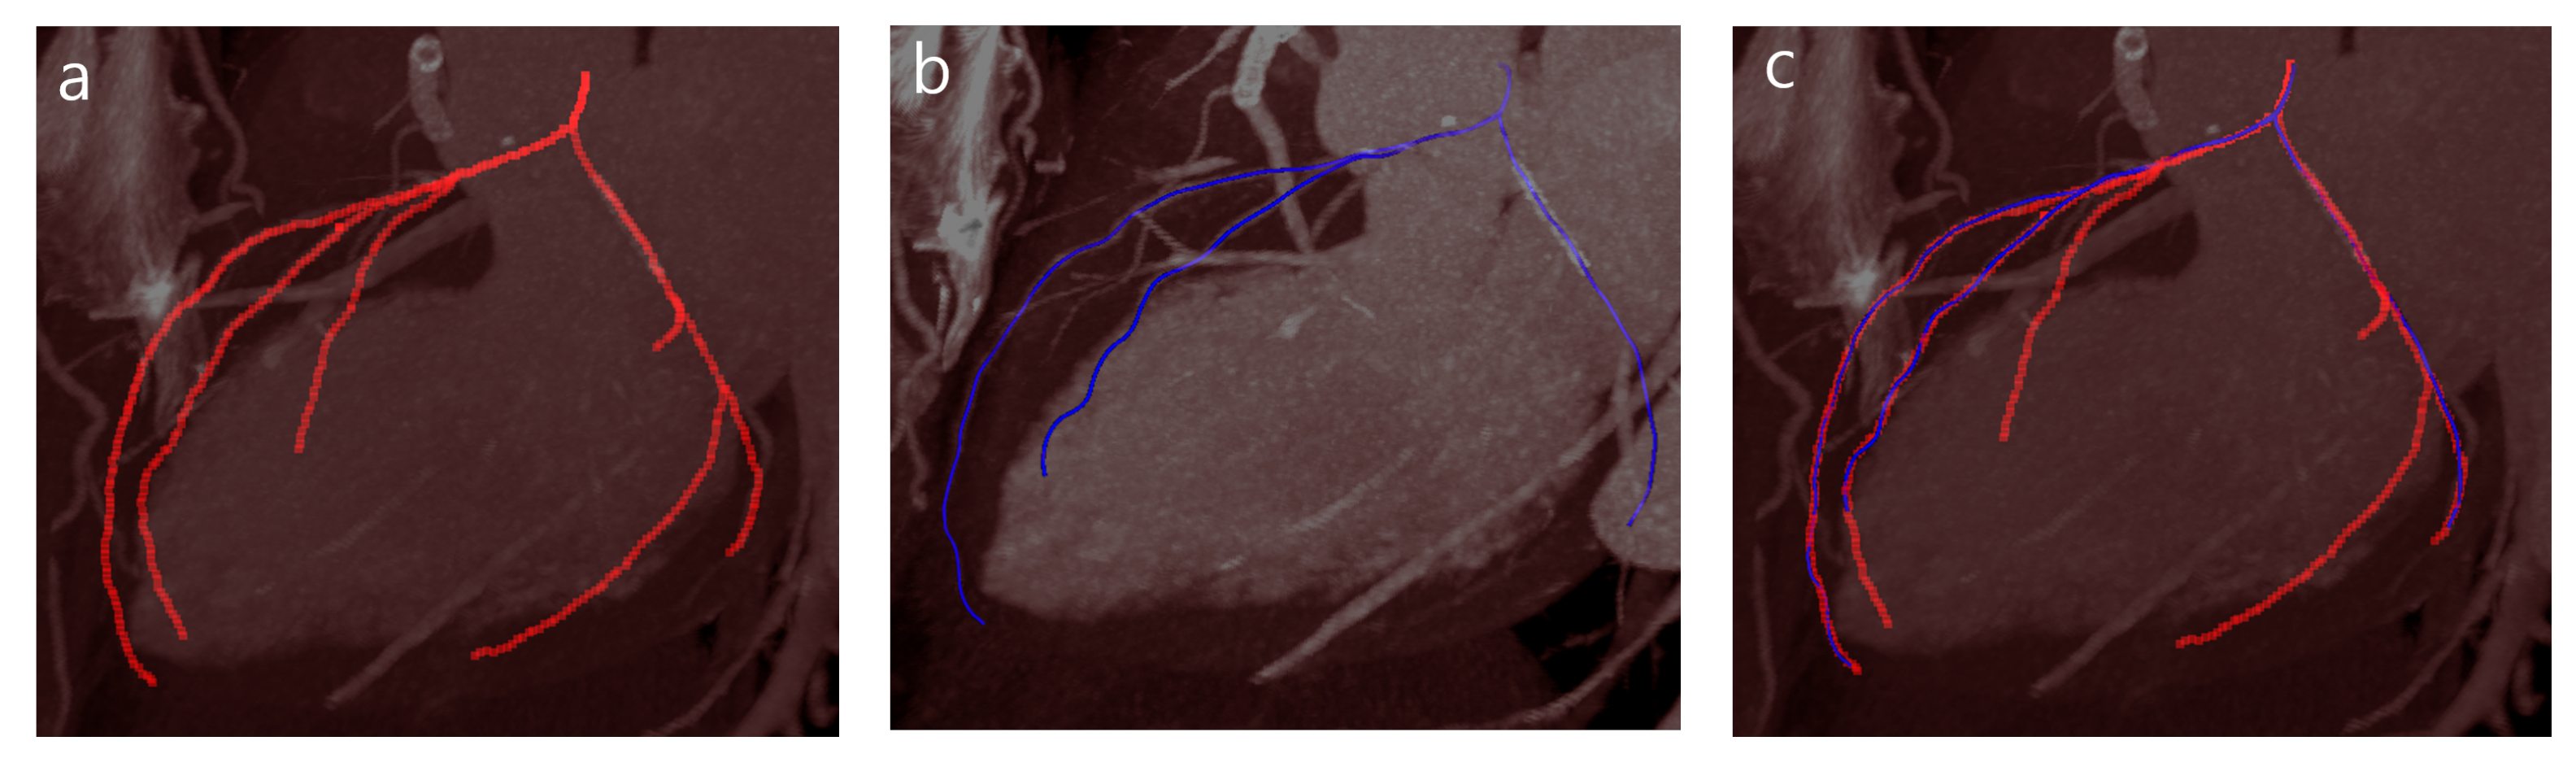

3.3. Evaluation on a CCTA Database

4. Evaluation and Results